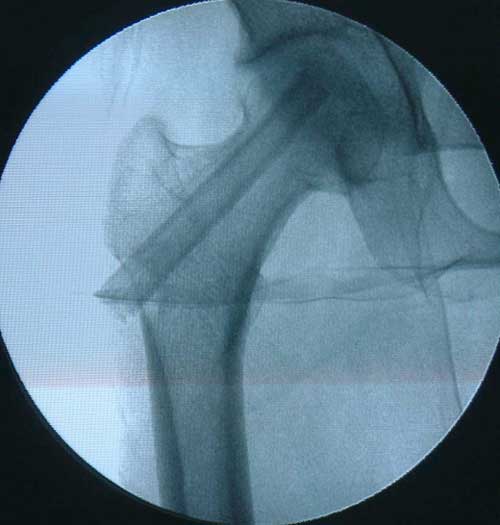

• 创伤轻微,切口仅为3—5CM,不损伤关节囊血液循环,关节活动功能好。对年轻的、中早期股骨头坏死的治疗有极大价值。

BMP植入,异体骨支撑,恢复形态     手术后24个月X线片,关节塌陷未加重,关节功能良好,无疼痛